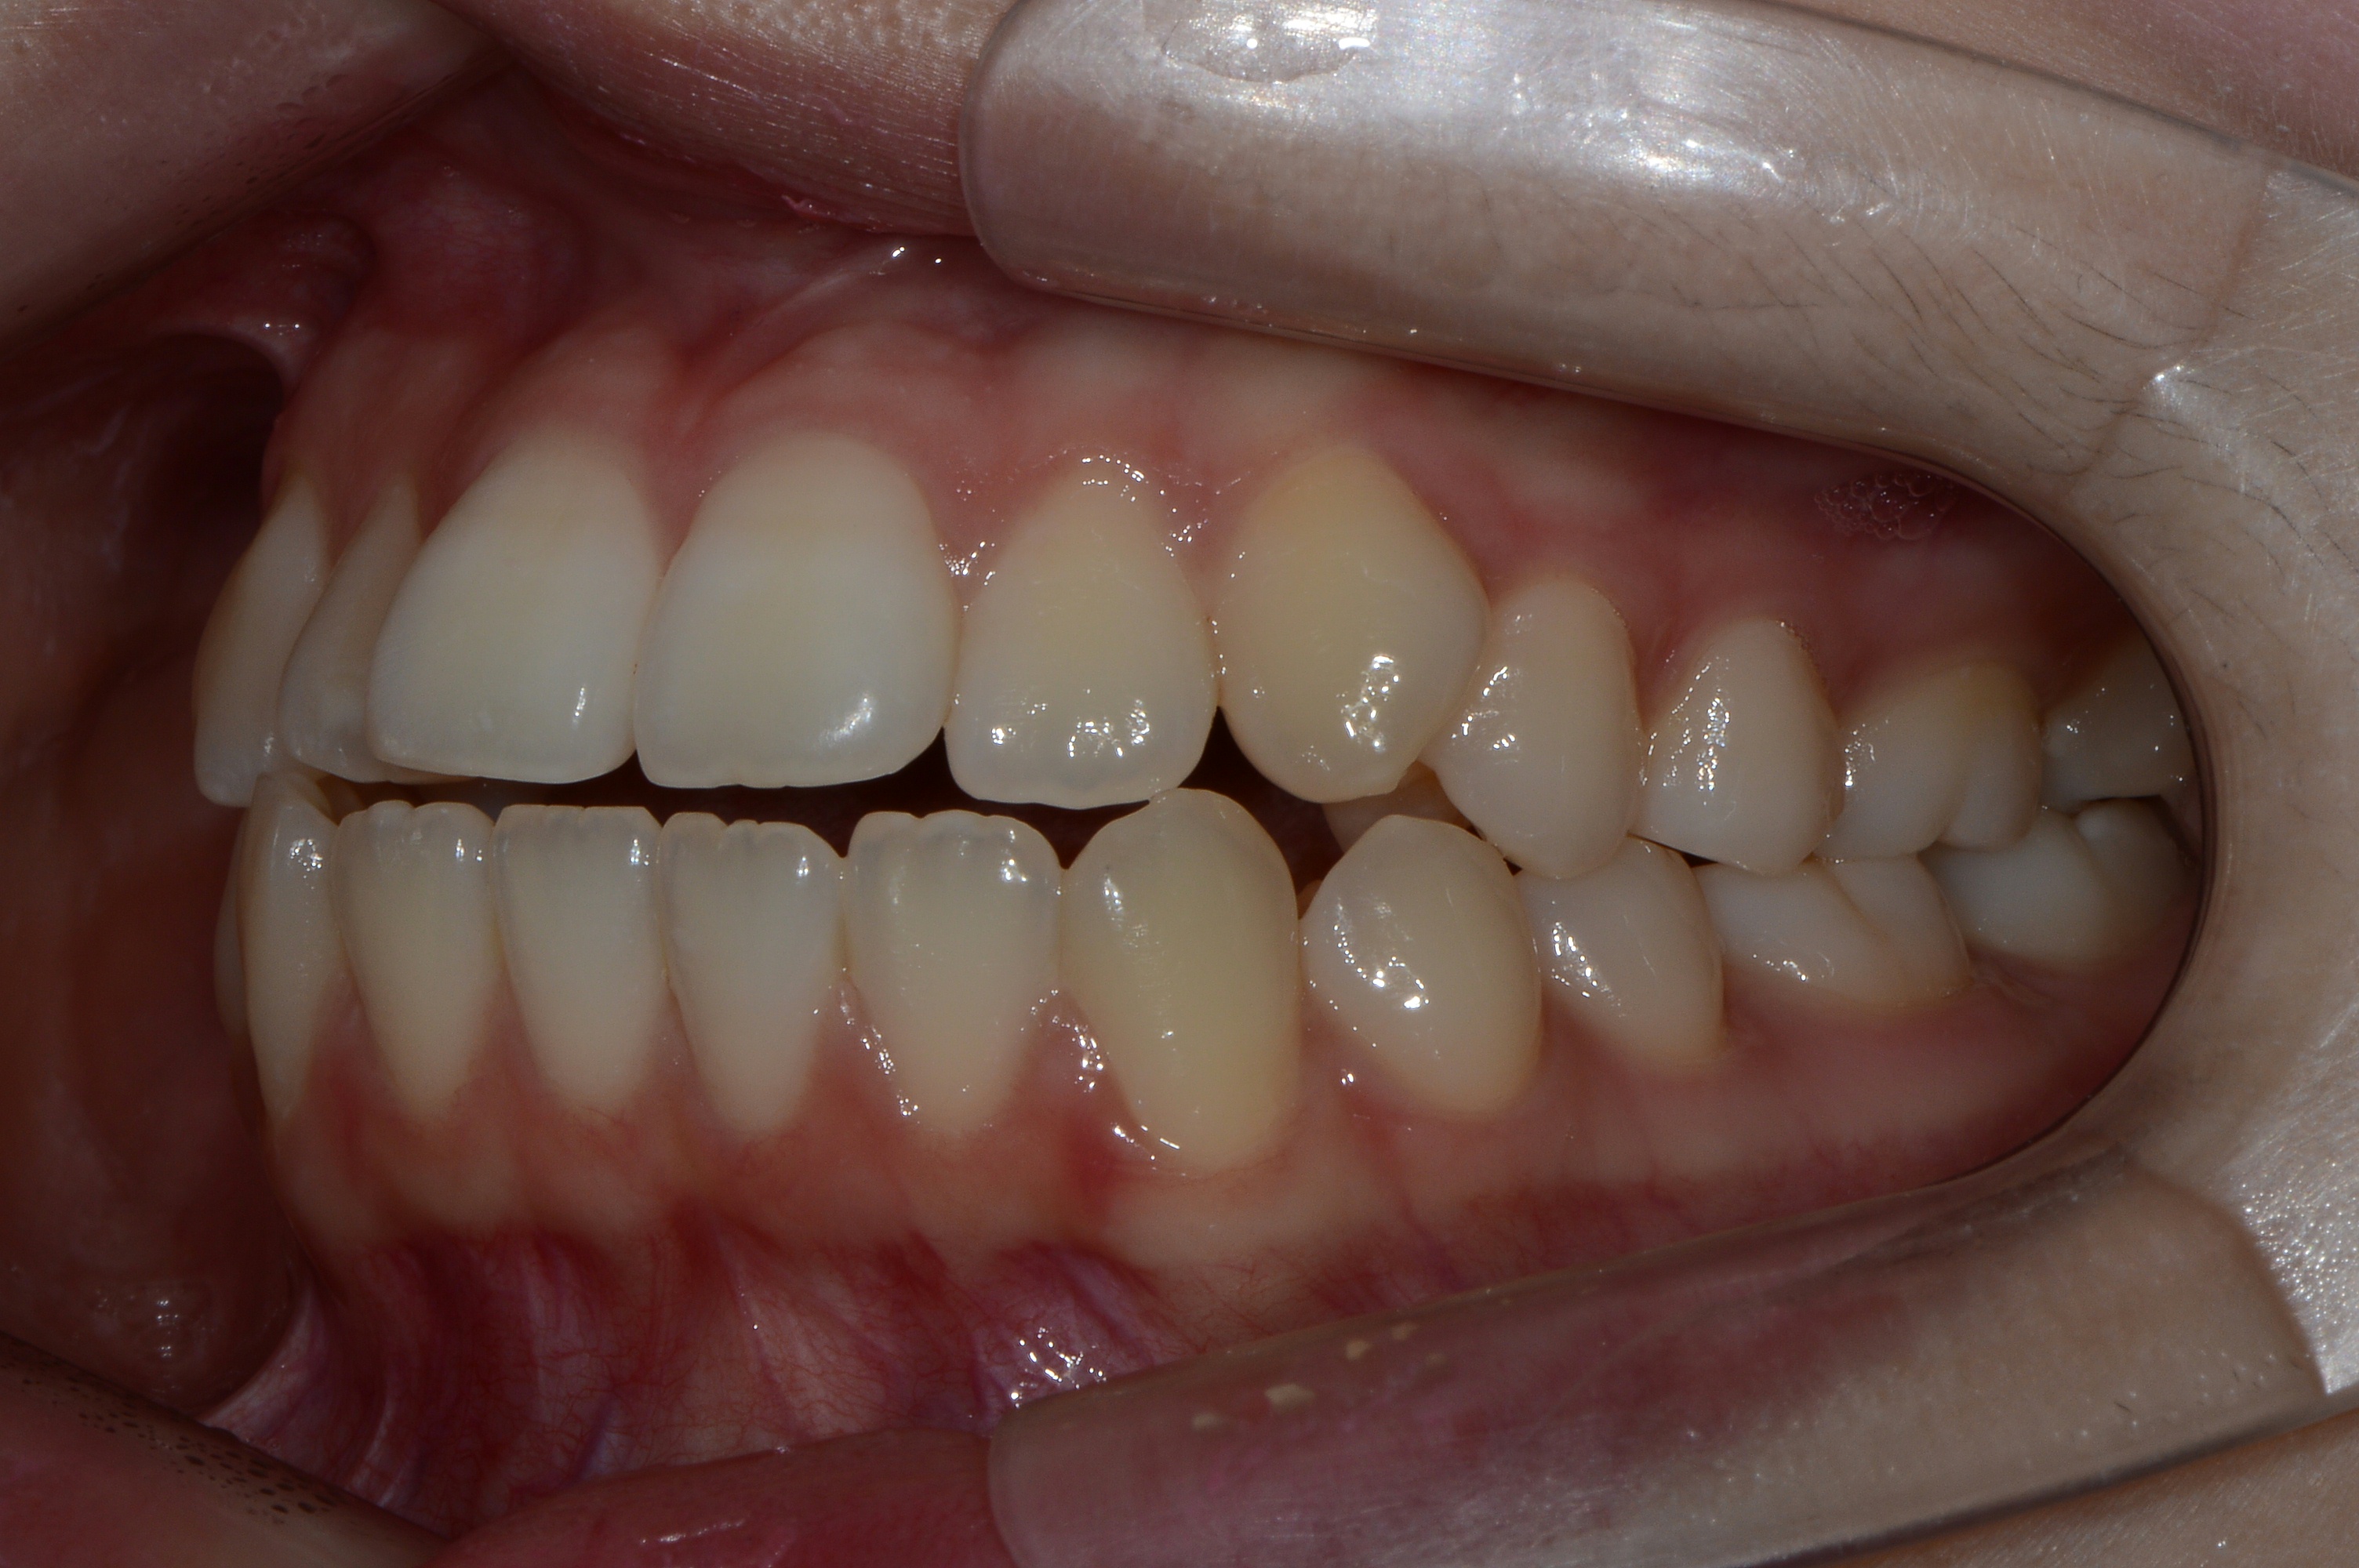

치료 후 사진입니다.